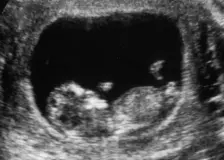

Nastávající rodiče se těšili na první snímky jejich dítěte. Lékaři po ultrazvuku spustili červený poplach

Mnoho nastávajících rodičů si nechá během ultrazvukového vyšetření vytisknout snímek svého nenarozeného dítěte. Někdy je však může čekat opravdový šok, když si ho prohlédnou. Někdy na snímku z ultrazvuku hledáte budoucího človíčka jen marně, jindy […